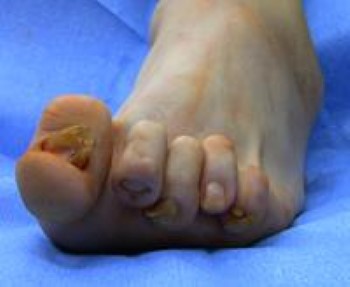

The changes that occur to the front of the foot are unique to patients with RA. These problems include:

Although each individual deformity is common, it is the combination of deformities that compounds the problem.

- The bunion is typically severe, and the big toe commonly crosses over the second toe.

- There can also be very painful bumps on the ball of the foot, creating calluses. The bumps develop when bones in the middle of the foot (midfoot) are pushed down from joint dislocations in the toes. The dislocations of the lesser toes (toes 2 through 5) cause them to become very prominent on the top of the foot. This creates claw toes and makes it very difficult to wear shoes. In severe situations, ulcers can form from the abnormal pressure.

The choice of treatment for patients with a bunion or lesser toe deformities (hammer or claw toes) depends on a number of factors.

- If the RA has progressed and the lesser toes (2 through 5) have dislocated, a complex operation to minimize the pain and restore the shape of the foot may be recommended. The operation involves fusion of the big toe and removing a portion of bone of each of the metatarsals. This surgery removes the prominent bone on the bottom of the foot that is a source of the pain and allows the toes to re-align into a better position.